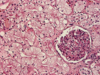

What do you see here?

Acute interstitial nephritis